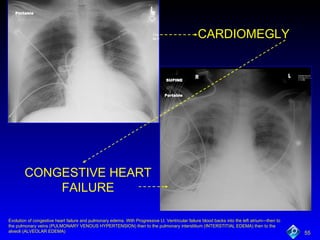

CARDIOMEGLY CONGESTIVE   HEART FAILURE Evolution of congestive heart failure and pulmonary edema. With Progressive Lt. Ventricular failure blood backs into the left atrium—then to the pulmonary veins (PULMONARY VENOUS HYPERTENSION) then to the pulmonary interstitium (INTERSTITIAL EDEMA) then to the alveoli (ALVEOLAR EDEMA)

Congestive Heart Failure Increased heart size:  cardiothoracic ratio  >0.5 Large hila with indistinct markings Fluid in interlobar fissures Pleural effusions, alveolar edema

• #56 Evolution of congestive heart failure and pulmonary edema. With Progressive Lt. Ventricular failure blood backs into the left atrium—then to the pulmonary veins (PULMONARY VENOUS HYPERTENSION) then to the pulmonary interstitium (INTERSTITIAL EDEMA) then to the alveoli (ALVEOLAR EDEMA)